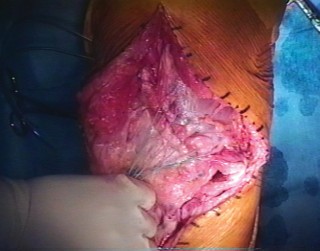

The previous midline longitudinal incision is utilized. Full-thickness fasciocutaneous flaps must be raised to preserve the subdermal vascular plexus. Subcutaneous dissection is strictly avoided to prevent skin flap necrosis. The arthrotomy is typically performed through the previous medial parapatellar approach.

The joint is thoroughly debrided of all fibrotic scar tissue, and the arthroplasty components are inspected. If the components are well-fixed and appropriately positioned, they are retained. The native, dysfunctional patella is typically excised, taking care to preserve the medial and lateral retinacular tissues for later closure and graft coverage. The native quadriceps tendon is identified, mobilized, and prepared to receive the proximal aspect of the reconstruction.

Allograft Preparation

When utilizing a Whole Extensor Mechanism Allograft, the graft is thawed in warm saline containing broad-spectrum antibiotics. The tibial bone block is meticulously shaped using an oscillating saw and a high-speed burr. A standard bone block configuration is approximately 2 to 3 centimeters in length, 1.5 centimeters in width, and 1.5 centimeters in depth.

The edges of the bone block are chamfered to reduce stress risers and to facilitate a press-fit insertion into the host tibia. Heavy non-absorbable cerclage wires or cables are passed through pre-drilled holes in the allograft bone block prior to insertion.

Tibial Host Bed Preparation and Fixation

A corresponding trough is created in the host anterior tibia, slightly medial to the native tibial tubercle to optimize the Q-angle. The trough is undersized by 1 to 2 millimeters to ensure a rigid press-fit of the allograft bone block.

The allograft bone block is impacted into the host trough. Fixation is achieved using the previously placed cerclage wires or cables, which are passed around the proximal tibia or through transverse drill holes in the tibial metaphysis. Supplemental fixation with anterior-to-posterior cortical screws can be utilized to enhance rotational stability and resist the massive pull-out forces generated during knee flexion.

Proximal Tensioning and Fixation

The most critical step of the procedure is the proximal tensioning of the graft. The knee must be placed in full, rigid extension. The allograft quadriceps tendon is draped over the host quadriceps tendon.

The reconstruction must be tensioned maximally. A common technical error is under-tensioning the graft, which inevitably leads to a profound postoperative extensor lag. Heavy, non-absorbable sutures (such as #5 or #2 ultra-high-molecular-weight polyethylene) are used to weave the allograft and host quadriceps tendons together using a Krackow or similar locking stitch technique. The graft should be tensioned such that the reconstructed patella sits at the appropriate joint line level, avoiding patella baja or alta.

If a synthetic mesh is utilized instead of an allograft, the mesh is secured to the proximal tibia using cementation into a prepared trough or via heavy suture anchors. The mesh is then passed through the host patellar tendon remnants, over the patella, and woven into the host quadriceps tendon under maximal tension with the knee in full extension.